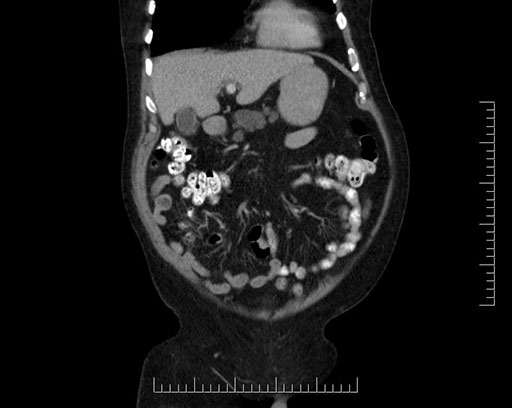

Whipple (pancreaticoduodenectomy) [case 7]

Imaging Analysis

Look through the patient's CT scan to identify any areas of concern for the necessary procedure.

Based on your CT findings, which issue(s) would give reason for "planned slowing down moment(s)" in this case?

Considering a standard Whipple procedure, what step(s) of the operation would you do differently in this case?